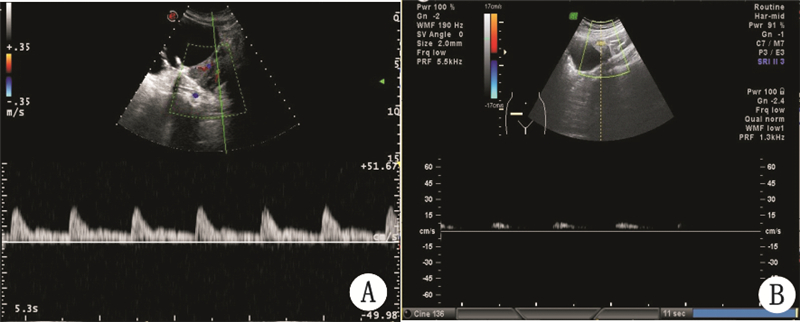

- 超声检查